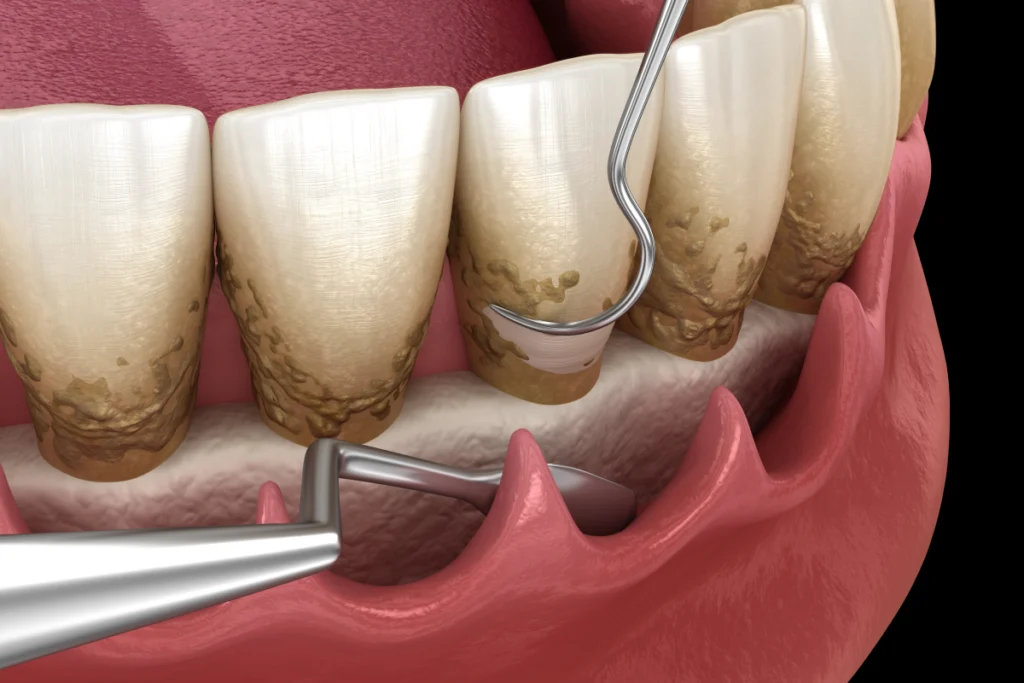

Lorsque la parodontite progresse, elle peut entraîner la formation de poches parodontales profondes, une perte osseuse et un déchaussement des dents. Dans ces situations, une intervention chirurgicale peut être nécessaire pour éliminer les bactéries et restaurer les tissus.

Cette intervention permet de nettoyer les zones profondes sous la gencive. Le praticien soulève délicatement la gencive, puis élimine le tartre résiduel et les tissus inflammatoires. Il nettoie les racines avec précision. Si besoin, il régularise certaines zones osseuses.

Avant toute intervention le docteur réalise un bilan parodontal complet afin d’évaluer précisément l’état des gencives, la profondeur des poches, la présence de tartre sous-gingival et l’éventuelle perte osseuse. Ce bilan permet d’établir un plan de traitement personnalisé, adapté à votre situation et à vos objectifs (santé, confort, esthétique).

- Examen clinique des gencives (saignements, inflammation, récessions)

- Mesure des poches parodontales